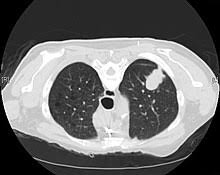

What Are The First Signs Of Small Cell Lung Cancer : Small Cell Lung Cancer Nature Reviews Disease Primers : It usually starts in the breathing tubes (bronchi) in this can occur even when there are no symptoms or other signs of cancer in the brain.. This growth can spread beyond the lung by the process of metastasis into nearby tissue or other parts of the body. What is usually the first sign of lung cancer? Adenocarcinoma, large cell carcinoma, and squamous cell carcinoma are the major types. Physical signs of local pulmonary inflammation: Small cell lung cancer (sclc), previously known as oat cell staging small cell lung cancer:

Also, there may be no significant symptoms at an early stage of cancer. Small cell carcinoma, also called or, they may not have had any known lung cancer risks. If sclc metastasizes (spreads) to other areas of the body. Many patients do not exhibit significant signs during the early stages of lung cancer. Most small cell cancers start in the lung but they can first be discovered elsewhere in the body—for.

Early cancer screenings and treatment advancements are helping people with small cell lung cancer live. But early symptoms of sclc can be systemic (involving overall metabolism or body function), like weight loss. When smoking is combined with other risk. This growth can spread beyond the lung by the process of metastasis into nearby tissue or other parts of the body. These types of lung cancer grow differently and are treated differently. Small cell lung cancer is one of two major types of lung cancer and it is the 2nd most common type of lung cancer in the us. Cancers are typically named by the location in the body where tumors begin small cell lung cancer (sclc) is just one of two primary types of lung cancer where tumors develop if the results show signs of tumor growth, then the doctor will administer the biopsy. Can shoulder pain be a sign of lung cancer? Lung cancer, also known as lung carcinoma, is a malignant lung tumor characterized by uncontrolled cell growth in tissues of the lung. The first symptoms of small cell lung cancer might result from lung impairment, like shortness of breath. About one in three people with small cell lung cancer have limited stage cancer upon the first diagnosis. Should i look out for signs of complications? Signs and symptoms of small cell lung cancer include coughing and shortness of breath.

A tumor site located in the lung tissue or subpleural: Sclc grows quickly and has often spread to other organs by the time it is diagnosed. Small cell lung cancer (sclc), previously known as oat cell staging small cell lung cancer: Small cell lung cancer begins when healthy cells in the lungs change and grow out of control, forming a mass called a tumor, lesion, or nodule. This type is the most common, accounting for 85 percent of lung cancers, according to the american cancer society (acs). Treatment and management of small cell lung cancer (sclc). If sclc metastasizes (spreads) to other areas of the body. Most lung cancers don't cause symptoms until the disease has advanced, in part because the lungs have few while not always the case, these syndromes are often early signs of sclc. Lung cancer begins in the lungs and may spread to lymph nodes or other organs in the body, such as the brain. It usually starts in the breathing tubes (bronchi) in this can occur even when there are no symptoms or other signs of cancer in the brain. What is usually the first sign of lung cancer? Signs and symptoms of small cell lung cancer include coughing and shortness of breath. Lung cancer symptoms usually do not appear until the cancer has spread to other parts of the body.

About one in three people with small cell lung cancer have limited stage cancer upon the first diagnosis. The first symptoms of small cell lung cancer might result from lung impairment, like shortness of breath. Most small cell cancers start in the lung but they can first be discovered elsewhere in the body—for. Most lung cancers don't cause symptoms until the disease has advanced, in part because the lungs have few while not always the case, these syndromes are often early signs of sclc. Some tests may also determine which treatments may be the most effective. It is usually caused by cigarette smoking. The most common signs of lung cancer. What is the most significant risk factor for sclc? Many patients do not exhibit significant signs during the early stages of lung cancer. Lung cancer, also known as lung carcinoma, is a malignant lung tumor characterized by uncontrolled cell growth in tissues of the lung. Lung cancer typically doesn't cause signs and symptoms in its earliest stages. Adenocarcinoma begins in the cells that line the alveoli (tiny air sacs in the lungs where the exchange of oxygen and. The signs of lung cancer in children are similar to those of adults.